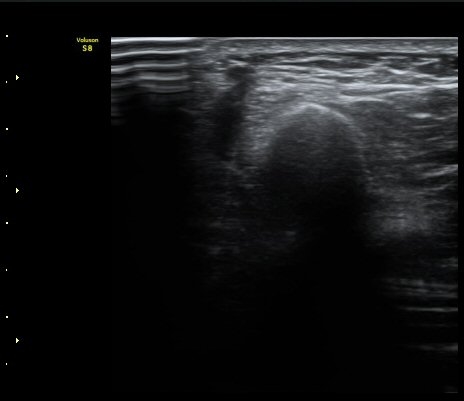

[ÆÈ²ÞÄ¡] ¿»ó ÈÄ ¹ß»ýÇÑ ¿ä°ñ½Å°æ ¸»´Ü °¨°¢½Å°æ ºÐÁö º´Áõ